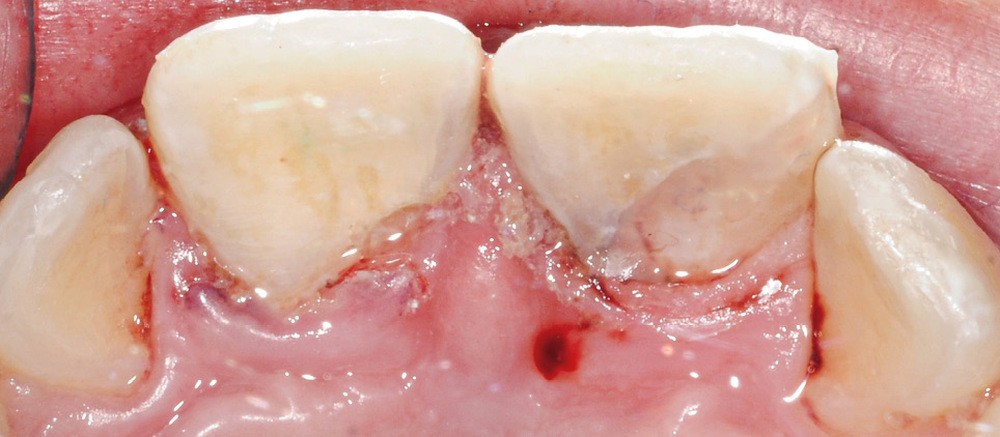

Les fragments sont placés dans du sérum physiologique afin de les réhydrater et d’augmenter leur potentiel d’adhésion. Dans un premier temps, des anesthésies locales en para-apicale de 11 et 21 sont réalisées. Des anesthésies de contact à l’aide d’un gel lidocaïné ou d’une cryoanesthésie peuvent être faites en amont pour diminuer les sensations désagréables de l’anesthésie locale. L’étape suivante consiste en la mise en place du champ opératoire. Au niveau du secteur antérieur, la mise en place d’une feuille de digue maintenue par des cordonnets élastiques de stabilisation (Wedjet™) est souvent réalisable. Sa mise en place est rapide et évite la pose d’un crampon sur des dents impliquées dans le traumatisme. Un crampon sur la 55 est également placé afin de maintenir la digue. L’étanchéité obtenue n’est pas toujours idéale et des spécificités liées à l’enfant compliquent sa mise en place, comme ici des dents malpositionnées ou en cours d’éruption (fig. 4). Après un nettoyage des dents fracturées et des fragments à replacer, une vérification du repositionnement correct de ces fragments est effectuée. Une pulpotomie partielle d’une profondeur d’un millimètre est réalisée sur la 11 à l’aide d’une fraise boule diamantée. Un biomatériau de type biocéramique (Biodentine™) vient coiffer la pulpe de 11 et 21 (fig. 5). Les bords amélaires sont ensuite soigneusement nettoyés à l’aide d’une microbrossette. En effet, l’adhésion se fera principalement entre l’émail de la dent fracturée et l’émail du fragment. L’épaisseur de biocérmique est réduite pour être la plus fine possible.

Du côté des fragments dentaires, une gorge est réalisée au niveau de la dentine afin d’aménager de la place au matériau positionné sur la dent. Les fragments sont ensuite mordancés (30 secondes pour l’émail, 15 secondes pour la dentine). Le morceau est abondamment rincé, légèrement séché à l’air doux puis tamponné avec une microbrossette neuve pour ne pas dessécher les surfaces. Un adhésif est ensuite appliqué et frotté vigoureusement sur la surface de collage du fragment puis photopolymérisé selon les conseils du fabricant. Des étapes identiques sont réalisées sur la surface de collage de la dent fracturée (mordançage, rinçage, séchage, adhésif, photopolymérisation). Afin de limiter les saignements, un cordonnet rétracteur imbibé d’un produit hémostatique tel que le sulfate d’aluminium peut être inséré dans le sulcus. Un composite fluide est appliqué sur la surface de collage du fragment dentaire qui est ensuite positionné sur la dent. Les excès sont éliminés à la microbrossette. Puis l’ensemble est photopolymérisé. Les fragments de 11 et 21 sont collés successivement (fig. 6 et 7). Les surfaces vestibulaires et linguales sont polies avec des disques pop-on (Sof-lex™, 3M) puis avec une cupule siliconée emplie de pâte diamantée (Diamond polish™, Ultradent). Une hypominéralisation est notée sur la 11, en lien avec la MIH du patient (fig. 6). Les hypominéralisations sont en effet des zones plus à risques de fractures. La prévention des conséquences de ces traumatismes par un procédé d’érosion-infiltration en profondeur est fondamentale [5]. Les propriétés mécaniques de cet émail affaibli en ressortent augmentées [6].